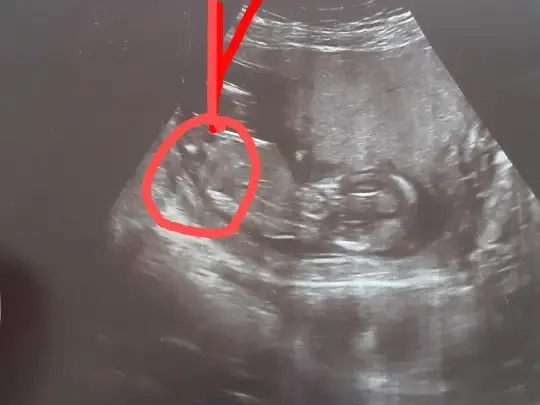

GöremedimIkra meyra banada yorum yapabilirmisin atmistim resim

Çok büyük gelmedi bana emin olamadım popoyada paralel değil acısı hafif dik geldi başka USG varsa teyit etmek isterimAttım tekrar bundan baslada yok 12+3

Başka yok sadece bu var tahmini hangiisnden yana kullanmak istersinÇok büyük gelmedi bana emin olamadım popoyada paralel değil acısı hafif dik geldi başka USG varsa teyit etmek isterimEki Görüntüle 2751139

Emin olamadım kiBaşka yok sadece bu var tahmini hangiisnden yana kullanmak istersin

Teşekkür ederim kese konumuna erkek demistin bakalim bu tutacak mı 3 kızım varEmin olamadım kiböyle usgler yanıttı beni %60 erkek derim